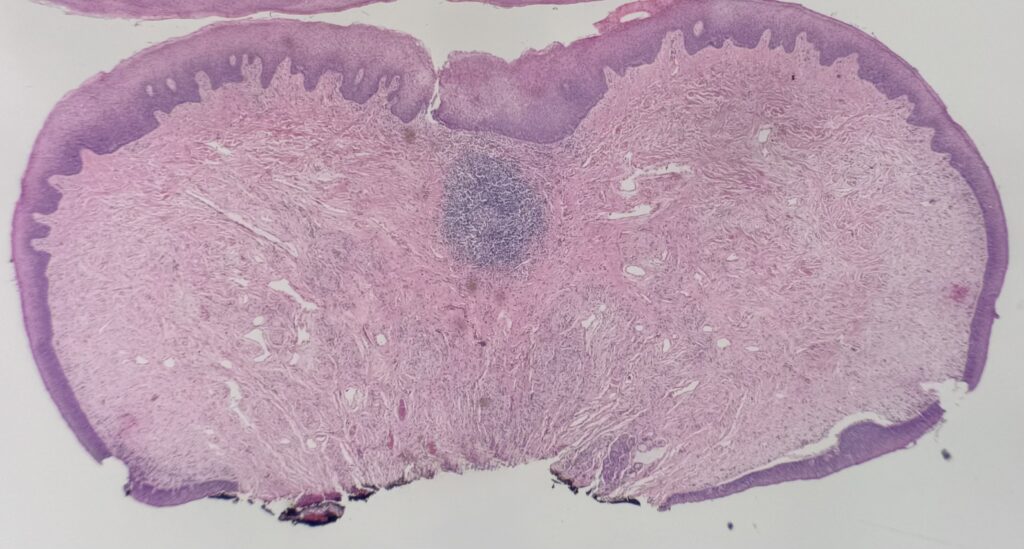

Histology:

Irritation fibroma – Benign reactive fibroblast proliferation that usually affects the lateral tongue and buccal mucosa. Histologic sections show a nodular, non-encapsulated proliferation of fibrous tissue with dense collagen bundles.

Traumatic neuroma – Benign proliferation of nerve bundles. Histologic sections show haphazard proliferation of neural structures at the base of the lesion (highlighted on S-100 stain).